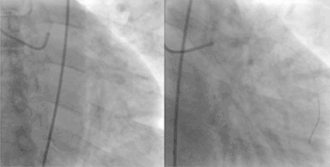

![]() Coronary arteries provide blood to the heart, originating from the aorta and surrounding the heart. Coronary arteries are subject to narrowing, resulting in reduced blood supply to the cardiac muscle. | |